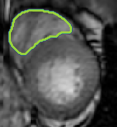

4.2 Visual assessment

We select the case that achieves the highest and lowest dice score for visual assessment. Fig. 4 shows example segmentation results where the proposed method achieved the highest agreement with the ground truth delineations. Fig. 5 shows example segmentation results where the proposed method achieved the lowest agreement with the ground truth delineations.